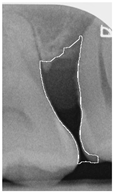

To ensure that only the area framing the symptom is preserved, and to remove the rest of the interfering areas or lines, the symptom frames are extracted according to the closure algorithm, i.e., the maximum connectivity area can be preserved to remove the frames of the non-symptomatic areas, as shown in Figure 7b. After the closure process, some of the frame lines are less smooth than others, which may affect the discrimination accuracy. To deal with this situation, this study performs the filling of the frame lines at the symptom area to facilitate the training of the model. Black and white are chosen to highlight the contrast and to compare the difference in discrimination between the two fill colors, as shown in Figure 7c,d.

Figure 7. Comparison of extracting the closed area and filling. (a) Close operation. (b) Extracting the closed area. (c) Filling with white. (d) Filling with black.